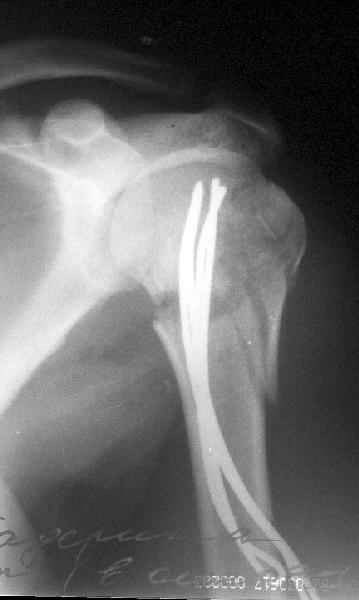

Сегодня взял больного повторно в операционную, не скажу, что повторная репозиция через неделю после первой попытки, была простая.

После удаления спиц попытался манипулировать отломками, но безуспешно, поэтому пришлось пользоваться периостальным элеватором, чтобы устранить смещение отломков и перепровести спицы. Проверил и перепроверил стабильность фиксации под ЭОПом, завтра Рг- будет готов, вот и поглядим....

Да. У нас довольно скромный опыт такого остеосинтеза (по 2 случая - плечо и наружная лодыжка), дошли до использования самого простецкого троакара, через который мы сверлим кость и вводим 6 мм стержни, когда накладываем аппарат. Соответственно, в качестве забойника отлично работает любой стержень от аппарата Илизарова. Еще из наших туземных особенностей - страшная любовь к спицевым дистракторам, поэтому делали в нем. Результат у этой дамы неизвестен, т.к. она из области и уехала рожать сразу после остеосинтеза, сейчас прошло больше 5 месяцев...

Что-то, наверно, сделали мы не совсем оптимально, поскольку у Анатолия Федровича и его соратников как-то красивее "раскрываются" спицы в головке плеча - надеюсь, он прокомментирует и подскажет, что надо подправить.